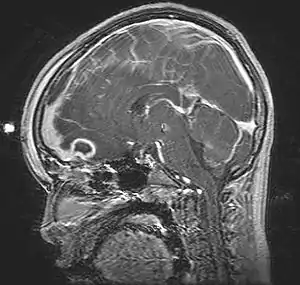

| Pott's puffy tumor, spreading towards person's brain. MRI, T1, sagittal, gadolinium contrast. | |

Pott's puffy tumor, first described by Sir Percivall Pott in 1760, is a rare clinical entity characterized by subperiosteal abscess associated with osteomyelitis. It is characterized by an osteomyelitis of the frontal bone, either direct or through haematogenic spread. This results in a swelling on the forehead, hence the name. The infection can also spread inwards, leading to an intracranial abscess. Pott's puffy tumor can be associated with cortical vein thrombosis, epidural abscess, subdural empyema, and brain abscess.